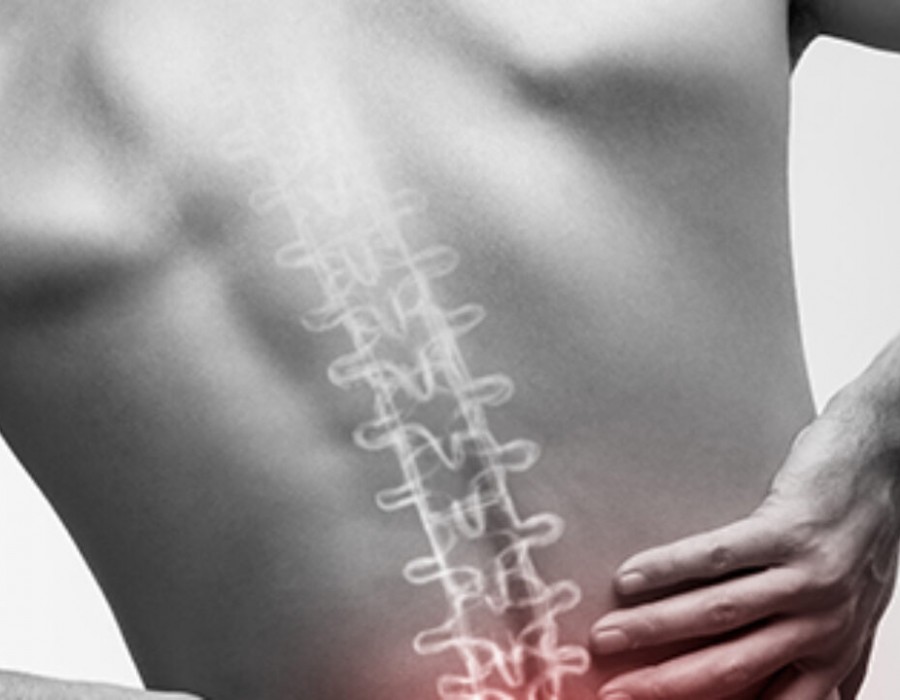

The most endemic is the lower back pain that is also named Lumbago and hits the lower end of the spine. Lower back pain is considered the single most common kind of disability around the world. The problem of back pain secures the position in the top 5 reasons why people visit the doctor for common ailments. This ailment is all-pervasive and almost every working adult has had or will have it in his or her lifetime. However, Back Center Ny can treat the condition without fail.

This common problem has its beginnings from very basic things like poor posture and the way we sit. Other than that, there are conditions like muscle spasms, muscle imbalances and most importantly synovial joints. The drying up of the synovial fluid could lead to a lot of friction between the discs and with constant pressure upon the lower back, the condition could be aggravated.

The normal indications of spinal pain are unexpected or ceaseless torment toward the back. This aggravation may be consistent or irregular, and at times, the aggravation might emanate to different regions. Of course, there are different kinds of agony included like puncturing, consuming sensations. There is a typical confusion that back aggravation influences just the spine. Instead, it can branch out to the arms and legs leaving them with a tingling sensation or weakness that might be constant or recurring. If you are dealing with such ailments it’s best to consult the Back Center.

These symptoms and the ailment itself can best be relieved by chiropractic methods. The techniques and treatments of chiropractic care for the treatment of ailments of the musculoskeletal system and back pain certainly fall under this category. There are several useful chiropractic methods for back pain but the most important one is the spinal manipulation method that targets the three joints of the lower spine. Spinal manipulation is intended to induce the release of para-spinal neurons through massages and also to maneuver the joints to bend opposing directions. This bending is done to increase the flexibility of the joint without breaking or damaging it.